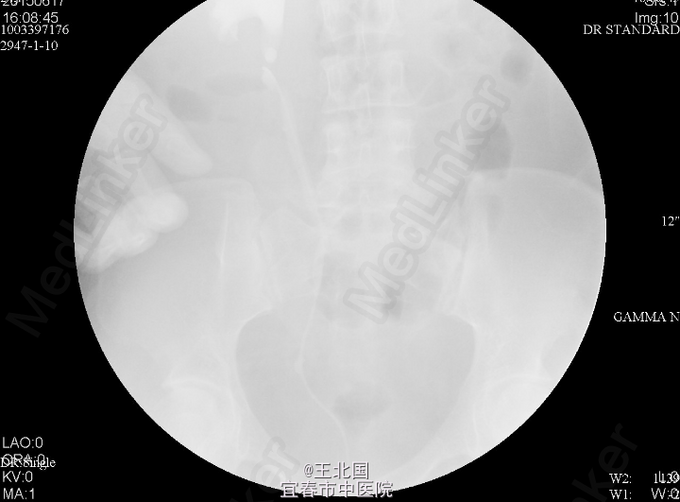

5、诊断:输尿管结石 6、处理:入院后完善相关检查:腹平片及静脉泌尿系造影均提示:右侧输尿管下段结石,右肾及右输尿管中重度扩张、积液,右肾功能减退低。行“右侧输尿管镜碎石取石术”,术中取尽结石后,见右侧输尿管迂曲,进镜及进导丝困难,后留置4F输尿管支架管一条。术后行泌尿道逆行造影,见右侧输尿管迂曲,造影剂通过正常。患者术后恢复可,顺利出院